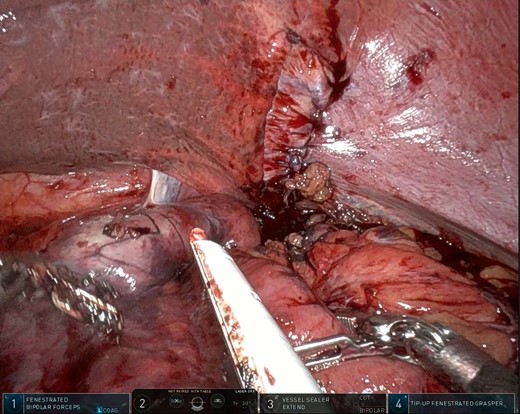

Thirty-seven days after the initial visit, the patient returned to the emergency department with burning epigastric pain that radiated to the left upper chest and hematemesis. Vital signs revealed tachycardia and hypertension. A comprehensive physical exam was significant for decreased breath sounds at the left base and tenderness in the left upper quadrant without signs of peritonitis. Pertinent laboratory findings showed leukocytosis with a left shift and thrombocytosis. A chest X-ray showed a significant portion of the gastric body in the left hemithorax (Fig. 1). A pulmonary CT angiogram found segmental and subsegmental pulmonary emboli in both lungs with no evidence of right heart strain and a left pleural effusion. A left diaphragmatic hernia with the “dangling diaphragm” sign can be seen on the sagittal view (Fig. 2). The coronal view shows discontinuity of the diaphragm and the “collar” sign (Fig. 3); the axial view shows the “dependent viscera” sign and thoracic fluid abutting abdominal viscera (Fig. 4).

After the pulmonary emboli were medically optimized, robot-assisted surgical repair was successfully completed with the da Vinci Xi system (Intuitive Surgical Inc.). Upon insertion of the camera and trocars, the stomach was noted to be contained within an 8-cm diaphragmatic defect. Gentle traction was used to reduce the stomach with some difficulty because of the significant portion of the gastric body that had herniated (Fig. 5) as well as adhesions that had formed within the thoracic cavity. Upon reduction of the stomach, the TDH was reapproximated in two layers with the second layer plicating the diaphragm because of the noted laxity (Fig. 6). A gastrostomy tube was placed, and a gastropexy was performed. Finally, a thoracostomy was performed at the left fifth intercostal space, and a chest tube was placed in the left pleural cavity and connected to vacuum suction. The patient tolerated the procedure well, and serial chest X-rays were taken to monitor recovery of the pneumothorax and pleural effusion (Fig. 7). The chest tube was removed, and the patient was discharged 10 days later in stable condition with instructions for a soft diet. The patient was well at the 2-month follow-up visit, and the gastrostomy tube was removed.

Intraoperative photo showing a large portion of the stomach herniating through the diaphragmatic defect. This photo shows the small portion that remained in the abdominal cavity.